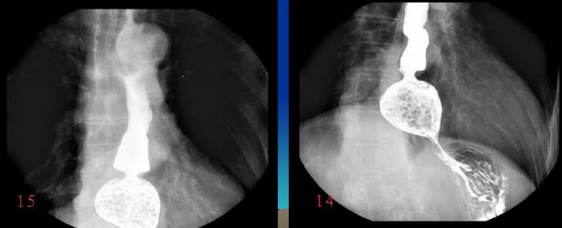

很多人没有接触到数字胃肠一体机,可能对它还比较陌生。其实它是一款多功能数字造影胃肠机,功能强大,操作便捷,可以真正实现数字化摄影,以及无胶片化管理,配置先进的工作站,可以保证其图像画质。同时它在临床上的应用也比较的广泛,能够检查多种疾病。下面,由普爱医疗小编详细列举一些。

3、气钡双重对比造影。